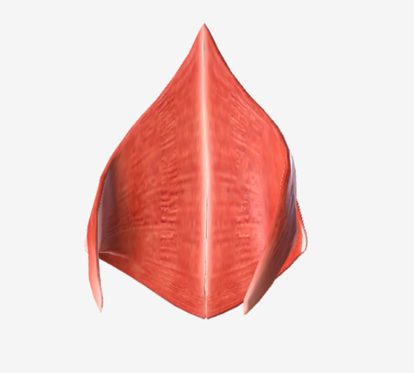

Superior pharyngeal constrictor

origin is on the pterygomandibular raphe, coursing posteriorly to insert on the median raphe of the pharyngeal aponeurosis function is to pull the pharyngeal wall forward to constrict the pharyngeal diameter